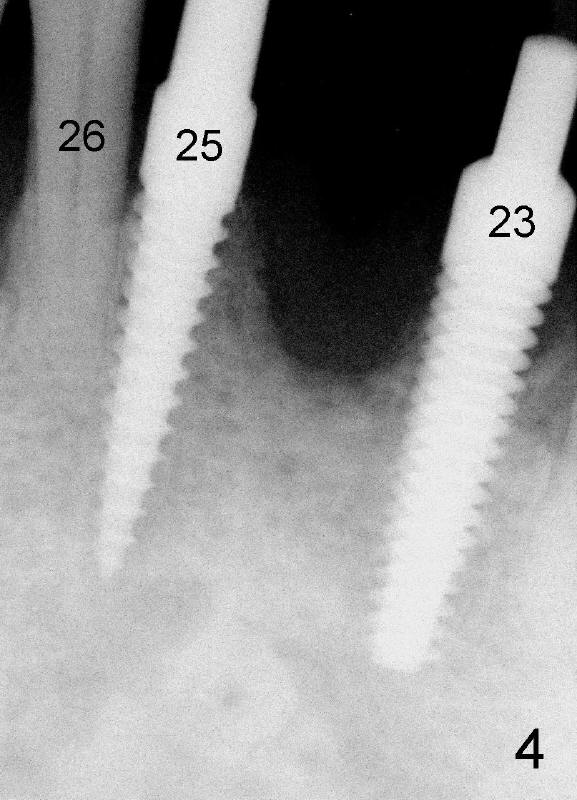

A 51-year-old man has history of periodontitis. The lower incisors have been splinted for several years. He lost a lower central incisor yesterday (Fig.1). The buccal plate of this missing tooth is atrophic. It is planned to have the remaining incisors extracted, place three of one-piece implants (4.0x17 for #23 and 3.5x17 for #25 and 26, Fig.2) and fabricate immediate provisional bridge. Any comments?

Dear Drs. Dunson and Borgner: Thank you for giving me invaluable advice, which I will use for future cases. In fact the teeth #23 and 25 were extracted last Thursday. The mesiodistal width of both roots is 3.5 mm, while the buccolingual 5 mm. It is presumed that a 4 mm implant should not perforate the buccal plate. On the other hand, the relatively large implant should fill most of the socket. Upon implant placement, the buccal plate does not feel to bulge or perforation, particularly in apical aspect, by tactile sensation. There is separation between the root of the tooth #22 and the pilot drill (1.5 mm) at the site of #23 whereas the space is limited between the pilot drill (2 mm) at the site of #25 and the root of the tooth #26. As Fig.4 and 5 indicate, a 4x17 mm one-piece implant is placed at the site of #23 and 3.5x17 mm at #25. A temporary bridge is fabricated between #23 and 25 and splinted to #22 and 27 (Fig.6). Since the abutment of the 4x17 mm one-piece implant is not tall, parallelism is not an issue after initial prep. The tooth #21 is missing. Do we still have to splint between #20 and #29 in one piece lingually?